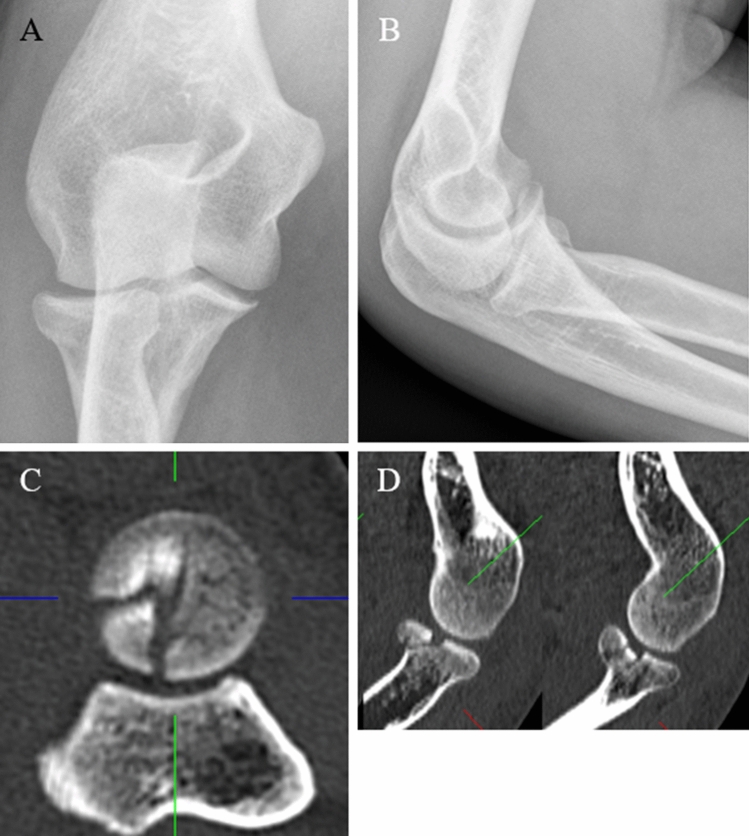

Fig. 1.

a, b Preoperative radiographs (lateral and anteroposterior) of a Mason type III fracture (Case1). c CT-scan in axial view and d in sagittal view showing the mutifragmental radial head